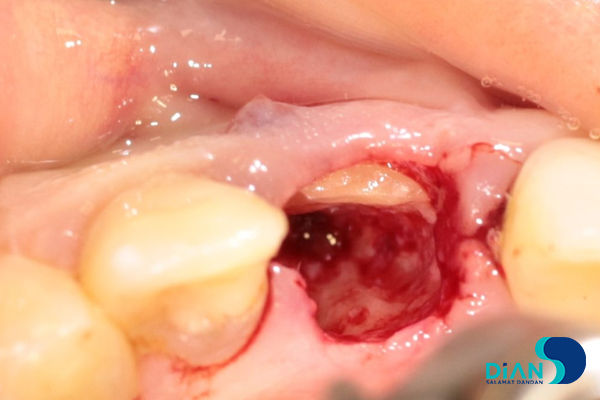

The alveolar socket was washed with antiseptic solution, and then the dentist made osteotomy while considering the future correct position of dental implant in the socket in relation to 12, 21 and 31 teeth.

He formed implant bed by following Bio3surgical protocols.

Bio3 implant Progressive 3.8/13 was entered from the box and fixed with 20-25 N/cm2 loading.

Cover screw was placed.

The gap between the implant and the tooth root was filled with bone material.